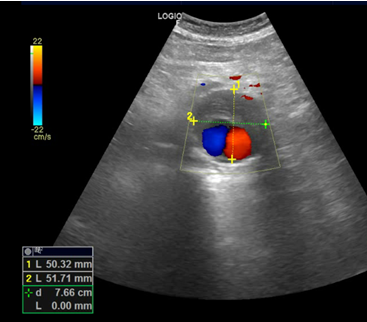

Exploramos con sonda convex en corte longitudinal en epigastrio una imagen ovalada de predominio anecoico de bordes bien delimitados que en corte transverso se extiende longitudinalmente por la linea media de forma ovalada y de diametro mayor a 93,3 mm que presenta contenido hipoecoico en semiluna adherido a pared altamente sugerente de aneurisma aortico con trombo endomural que en algunas zonas ocupa más del 50% de la luz del vaso.